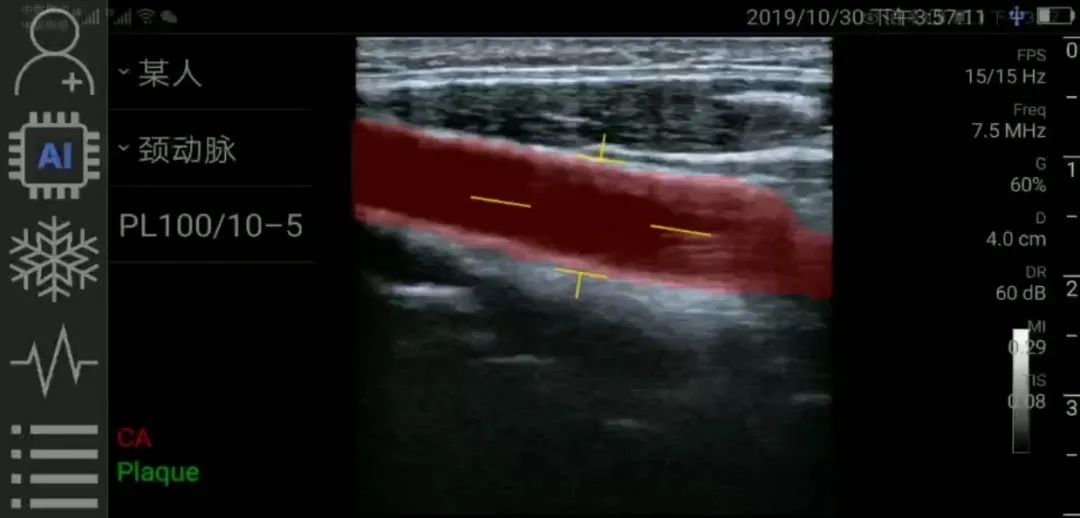

一键测量,智能手持超声“观”诊器

就在你的手机上

探头+手机,

安全,轻巧,方便,

插上手机随时随地使用。

一键AI辅助,

超声天书一目了然,

人人都能看懂。

一键AI测量,

像血压计、温度计一样,

读数即可知道异常。